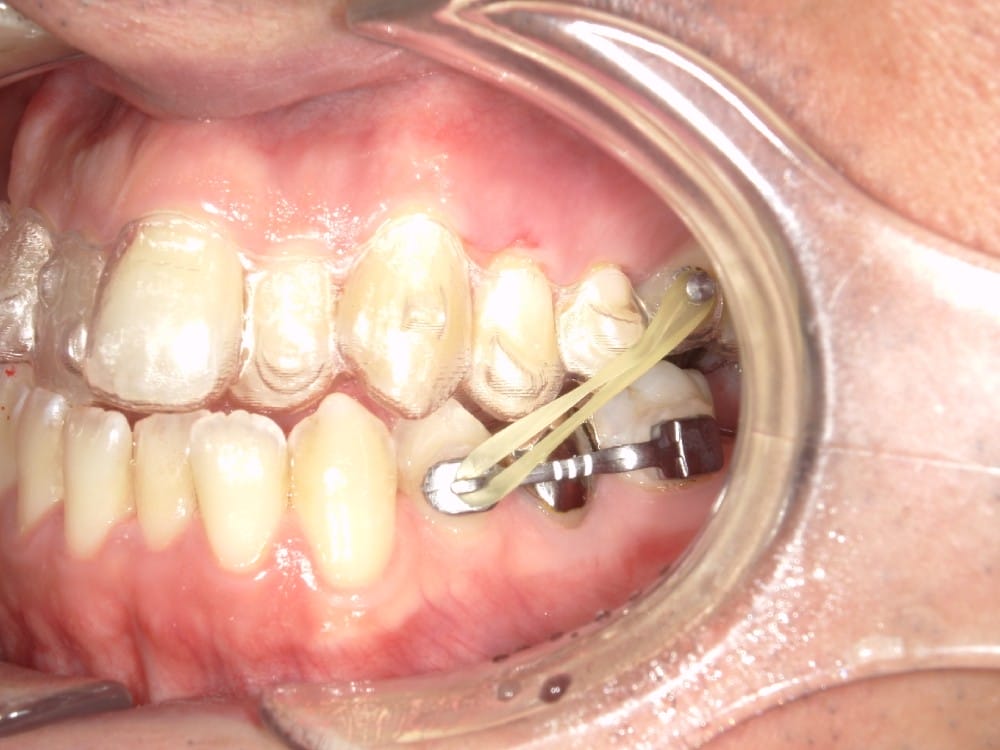

このような奥歯の移動量が大きい症例では、マウスピースだけでは難しいことがあり、カリエールとよばれる装置を補助的に使用し、上下の噛み合わせの前後関係を整えることで、手術を行わずに機能面と見た目の両方が改善することがあります。

一時的に前歯は噛み合わせが開いていますが、受け口の矯正では、最終段階で前歯ばっかりあたって奥歯がしっかり噛まないということも起こりやすいので、あえて狙って動かしています。

今回のケースも奥歯の移動量が大きいため、マウスピースだけでは難しいと判断し、カリエールとよばれる装置を補助的に使用し、上下の噛み合わせの前後関係を整えることで、手術を行わずに機能面と見た目の両方が改善することにしました。